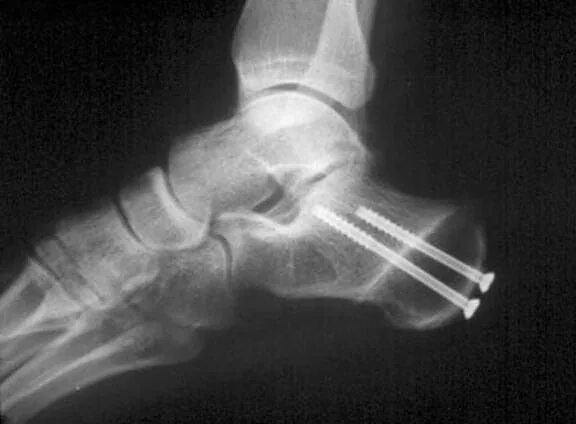

Пяточная остеотомия